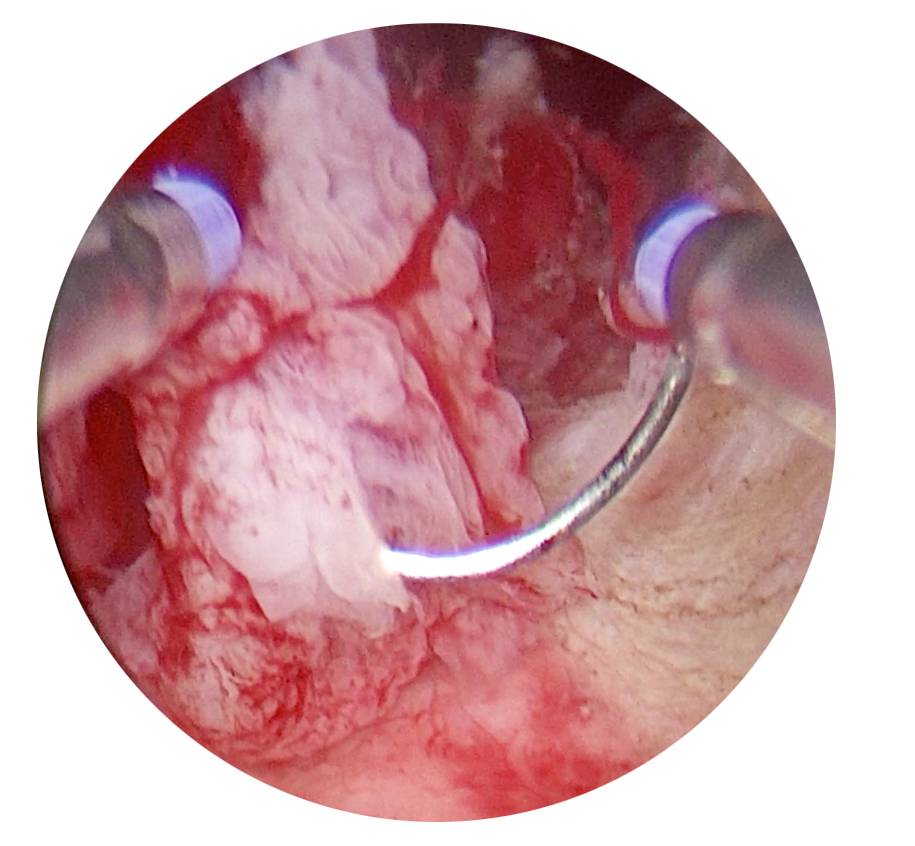

L’utilisation d’instruments 3mm sans énergie préserve l’endomètre de vos patientes. Même dans le cadre de pathologies majeures telles que les fibromes calcifiés de grandes tailles ou des cloisons utérines complètes, la performance de ces instruments rigides vous permet une prise en charge rapide et efficace.

Un seul temps opératoire, même pour les chirurgies complexes

Retrouvez la puissance de vos instruments de mini-coelioscopie pendant votre hystéroscopie. L’efficacité et la précision des instruments rigides de 3mm réduisent la durée des interventions.